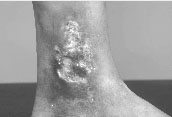

The blood supply of the leg consists of blood vessels called veins that return blood from the lower legs to the heart, assisted by valves that ensure that the “one-way” upward flow of blood. In many patients with venous leg ulcers, these valves are not working properly, causing blood to “pool” in the lower legs. This can lead to swelling and darkening of the skin, and eventually to venous leg ulcers (Figure 4).

Fig 4 Venous Leg Ulcer - The skin of the leg can turn dark brown or red.

The ulcer is usually wet and weepy, with heavy discharge.